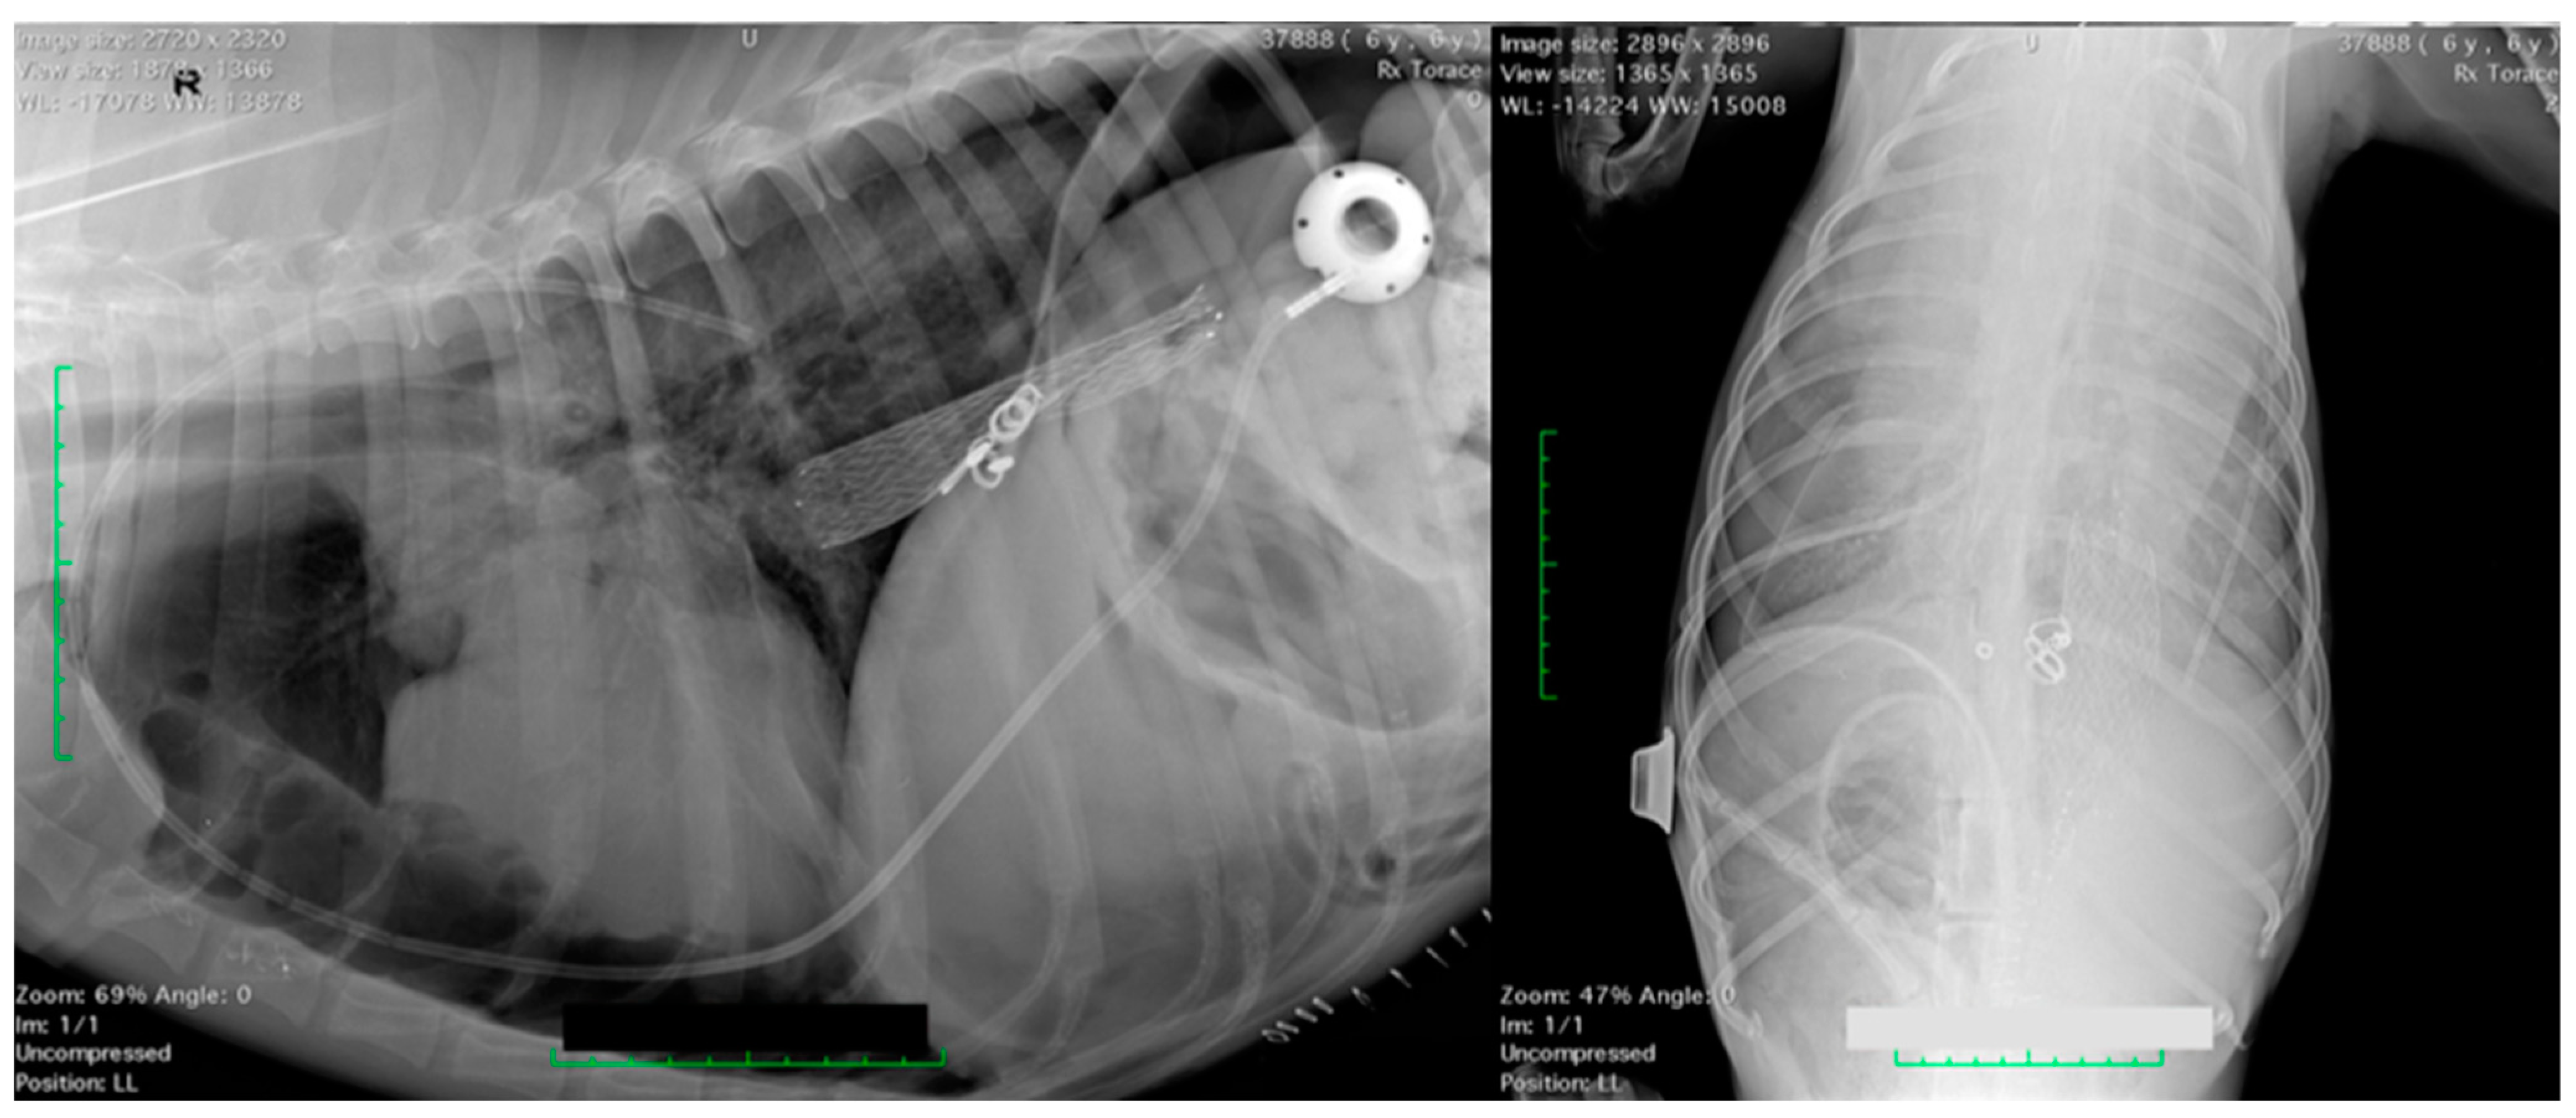

2.1. Surgical Procedure

| Case | Signalment | PleuralPort | Surgical Time | Diagnosis | Complications | Outcome |

|---|---|---|---|---|---|---|

| 1 | 11 yo FN Yorkshire | 2 | 55 min | Malignant mesothelioma | None | Euthanasia after 4 months |

| 2 | 8 yo MN German Shepherd | 1 | 80 min | Malignant mesothelioma | None | Euthanasia after 5 months |

| 3 | 8 yo FN Italian Greyhound | 1 | 35 min | Malignant mesothelioma | None | Euthanasia after 6 months |

| 4 | 10 yo FS Doberman Pincher | 1 | 45 min | Malignant mesothelioma | None | Euthanasia after 5 months |

| 5 | 14 yo ME mixed breed | 1 | 55 min | Malignant mesothelioma | None | Euthanasia after 5 months |

| 6 | 15 yo FN Yorkshire | 1 | 45 min | Pleural carcinomatosis with pulmonary metastasis and neoplastic pleural effusion | Port obstruction after 45 days | Euthanasia after 5 months |

| 7 | 13 yo ME Dachshund | 1 | 45 min | Chronic chylothorax | Pneumothorax immediately after port placement and for 12 h | Resolution after 355 days |